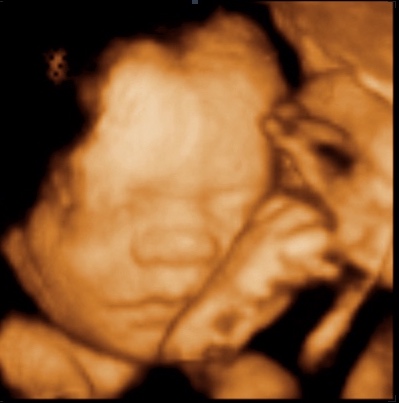

My boyfriend and I came to UC BABY yesterday at 27 weeks 2 days to see our little man with our mothers and my sister. So happy that I did totally worth the money and the experience. Makes it all so real. Getting even more excited to meet our little man in November. 5 stars! - (Facebook Review | 25 August 2017)

I had the most amazing experience of my life (so far)!!! The only better thing will be meeting my sweet boy. The staff are lovely. They make you feel so much at home. So warm and welcoming and so friendly. Seeing my boy's face on the screen was absolutely wonderful. I highly recommend UC BABY!!! Simply wonderful! - (Website Testimonial Submission | 3 Dec 2016)

We opted for the Golden Package and received excellent and super friendly service at both visits! During our first visit, baby was sleeping and facing backwards for most of the 30 minute visit. The technician kept us for nearly 50 minutes to give us a chance at extra pictures, as they didn't have anyone scheduled for the time slot right after us. On our second appointment, I brought my mom along, and the same technician asked her if there was anything special she would like to see on the screen while she was there. I thought that was very sweet, and my mom just loved the entire 3d ultrasound experience! Thank you so much for a very special and memorable experience! I will definitely be back should we have another baby in the future. 5 stars! - (Google Review | 8 Aug 2016)